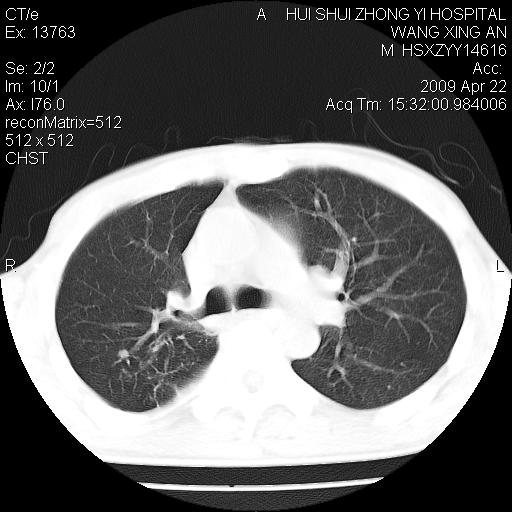

标题: CT19534:患者男、46岁咳嗽、胸痛半月。 [打印本页]

标题: CT19534:患者男、46岁咳嗽、胸痛半月。

1、右下肺中央型肺癌并右肺转移,右肺下叶不张。(肿块围绕右肺下叶支气管生长,致管腔闭塞右肺下叶不张;右肺有结节影)。

2、右侧胸腔积液。

3、右中上肺陈旧性肺结核(右肺见纤维化病灶及点状钙化)。